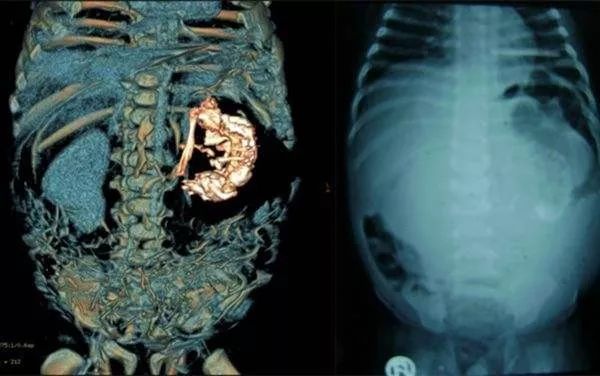

为一探究竟,张燕教授等将囊肿切开,却意外发现一个类似胚胎的组织,其中还有毛发、脂肪、骨头等物质。张燕教授初步推断,这是一个畸胎瘤。术后的病理检查证实,这是一个“卵巢成熟型畸胎瘤”(良性肿瘤)。

下图可能引起不适!!!

一岁半的小女孩,却莫名其妙的腹大如鼓。多方排查,方知竟是藏在她肚子里的“胎儿”在作祟。罕见的是,依靠掠夺她的营养,这个“胎儿”还发育出了毛发、骨骼等组织,面部骨骼轮廓也清晰可见。

刘修恒、程凡两位专家联手手术,于卿卿腹腔内发现了一直径约为20公分的巨大肿瘤。从中抽取出600余毫升的白色粘液后,才将肿瘤顺利取出。医生将瘤体切开,却意外发现一个类似胚胎的组织,其中还有毛发、骨头等物质,头骨上面还有两个眼窝。

医生推断,这是一个罕见的寄生胎,瘤体其实是一个发育不全的胎儿。幸运的是,揪出这一祸首后,卿卿已恢复健康,痊愈出院。